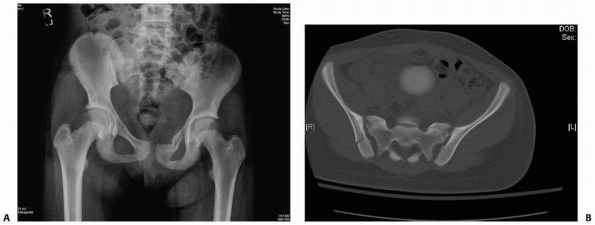

![]() |

FIGURE 20-16 A potentially unstable pelvis fracture with anterior and posterior injury. A. The radiograph shows a left superior and inferior ramus fracture. B.

The CT scan shows a minimally displaced fracture adjacent to the sacroiliac joint. This is also an example where both CT and plan radiographs can be used to evaluate the injury and help decide on displacement and treatment. This patient was treated nonoperatively with follow-up making sure there was no displacement. |